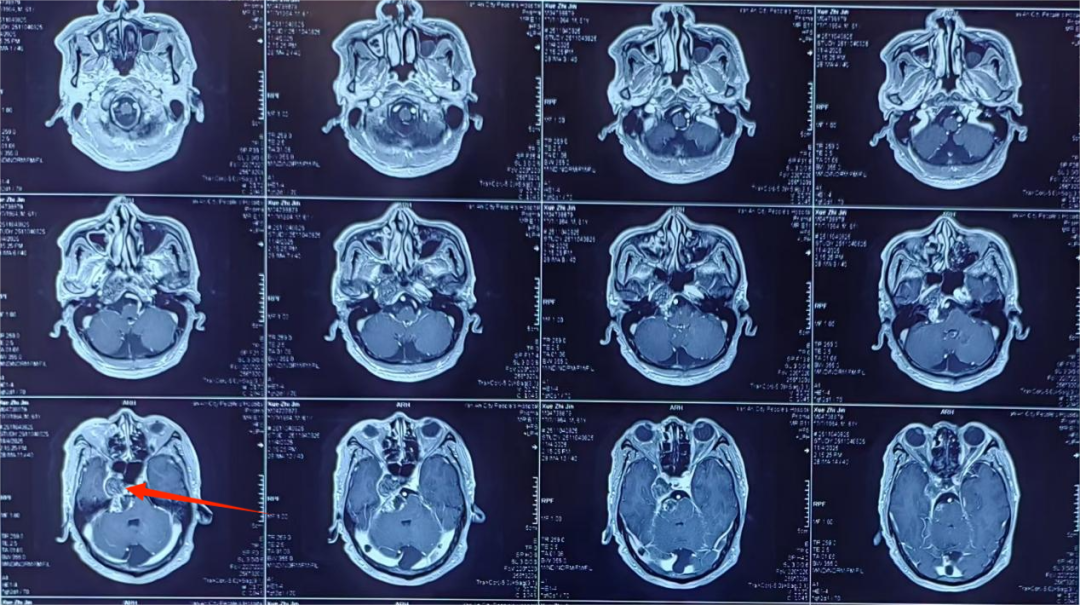

患者薛大爷(化名)一年前便出现右侧听力下降、面瘫以及右眼不能外展等症状。在外院进行头颅磁共振检查后,被考虑为右侧桥小脑角占位。由于该占位毗邻脑干,手术风险极高,家属出于安全考虑,仅让薛大爷接受了放射治疗。然而,一周前,薛大爷突发恶心呕吐,遂来到西安市第九医院神经外科二病区就诊。

入院后,医院为薛大爷完善了颅脑影像检查,结果令人揪心:右侧桥小脑角区肿瘤已明显挤压脑干。脑干,素有“生命的禁区”之称,其功能一旦受损,不仅会严重影响患者的生活质量,甚至可能危及生命安全。

面对如此复杂且凶险的病情,神经外科学科带头人、神经外科二病区主任郭清保对薛大爷的病情进行了详细评估。他指出,患者脑干已受到压迫,而桥小脑角区解剖结构复杂,肿瘤不仅明显挤压脑干,还压迫右侧颈内动脉颅内段。更为棘手的是,患者此前接受过放疗,导致肿瘤与周围组织严重粘连,分离过程中极易出血,手术难度堪称巨大。